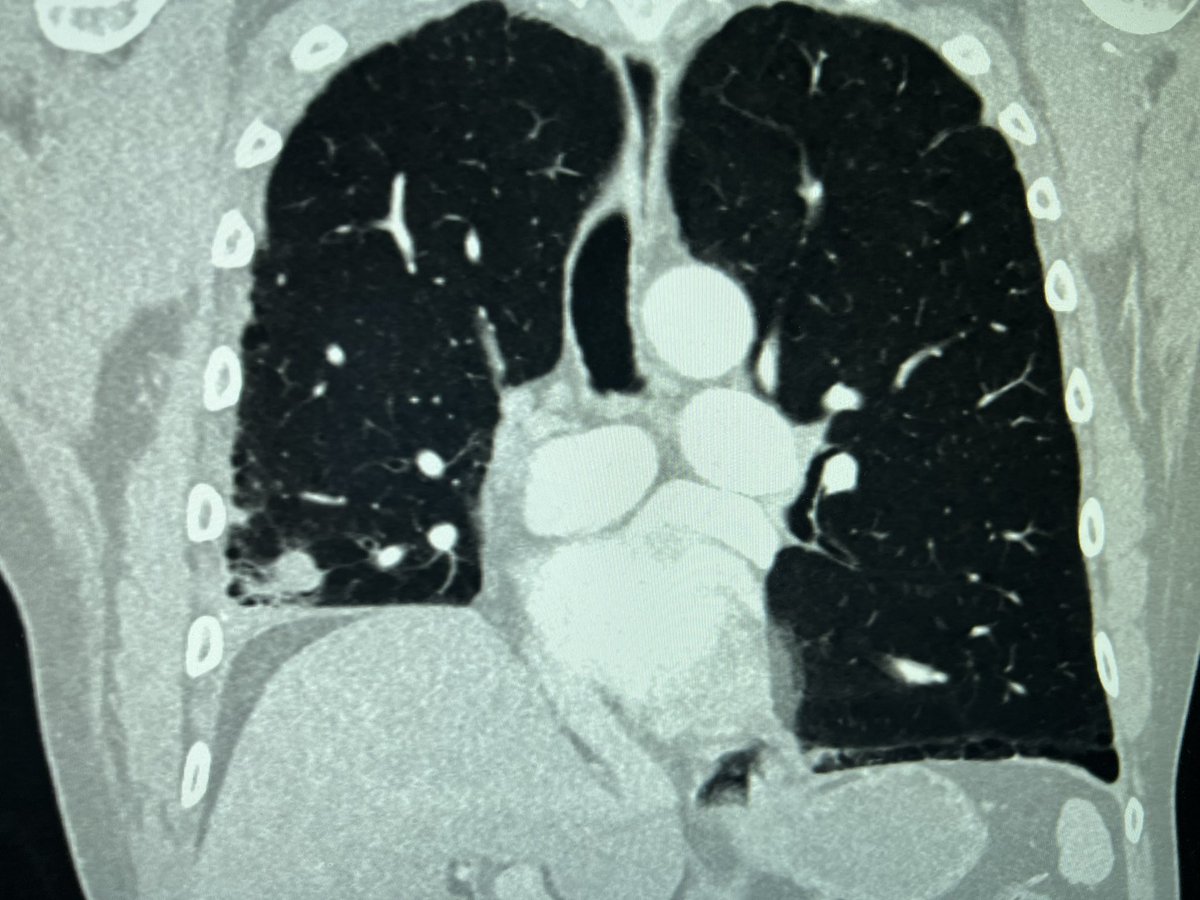

C-TRACT: a vital study for chronic blood clots. Visit bloodclotstudy.wustl.edu/c-tract/ to learn more. #patientcare #bloodclots #clinicalresearch #DVT